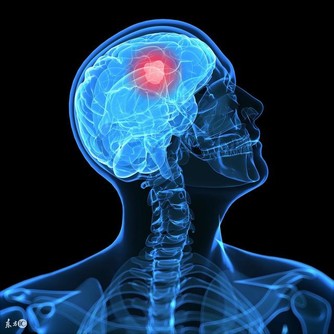

5. 甲狀腺功能低下

甲狀腺負責調節身體的代謝率,當甲狀腺功能低下時,基礎代謝率下降,身體產熱量減少,就容易出現怕冷、手腳冰冷的情況。如果長期有此問題,建議諮詢醫生進行甲狀腺功能檢查。